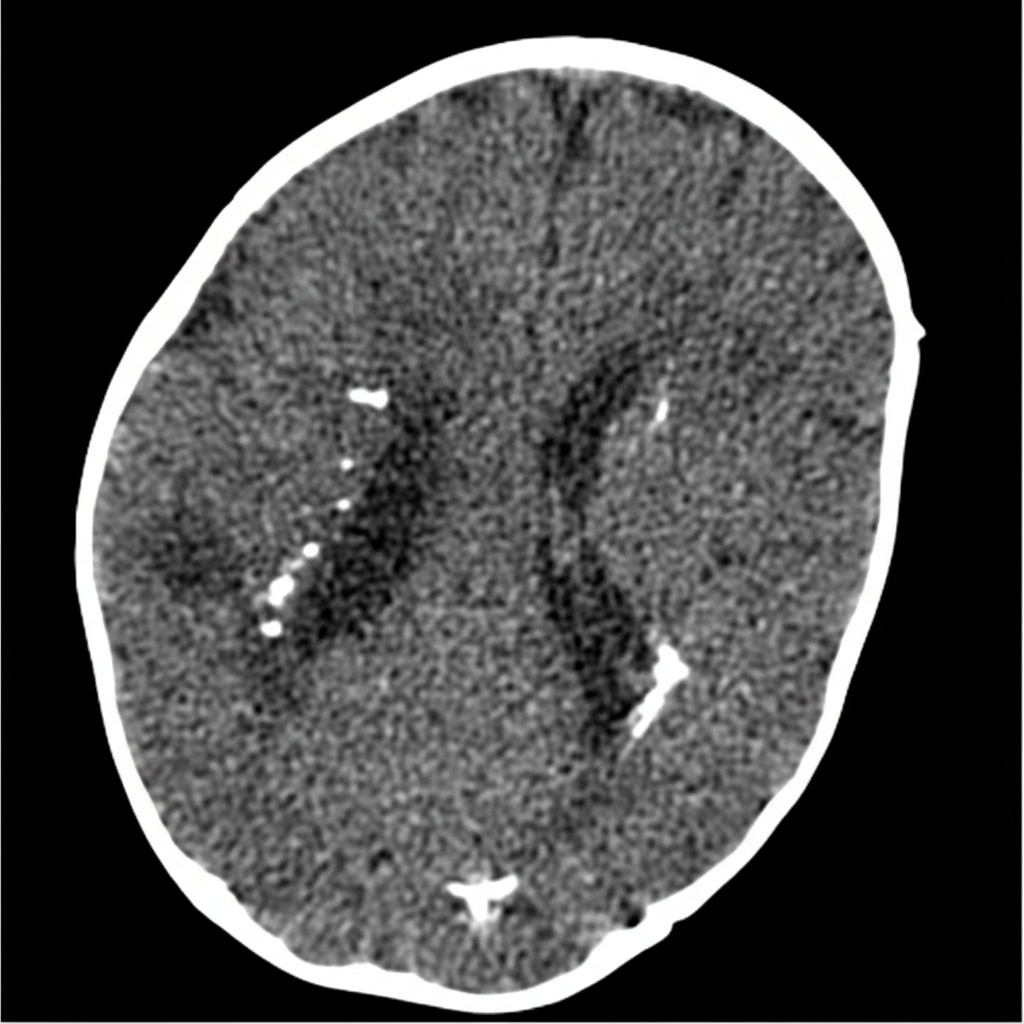

A 2-day-old boy, born at 38-weeks gestation, presents with jaundice and microcephaly. Social history reveals his mother is an animal caretaker. The vital signs include: temperature 37.0°C (98.6°F), blood pressure 75/40 mm Hg, pulse 150/min, respiratory rate 40/min, and oxygen saturation 99% on room air. Physical examination reveals hepatosplenomegaly. A CT and MRI of the head are significant for the following findings (see picture). Which of the following diseases contracted during pregnancy is the most likely cause of this patient's condition?